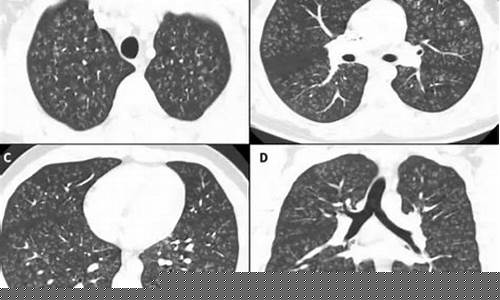

电子烟肺状态的变化

使用电子烟后,部分用户可能会出现肺部不适症状,尤其是长期使用者。常见的症状包括咳嗽、呼吸急促、胸部不适等。电子烟中的化学成分可能会引发类似慢性支气管炎的症状,甚至导致肺部细胞的损伤。更严重的情况下,长期吸入电子烟烟雾可能增加患慢性阻塞性肺病(COPD)等肺部疾病的风险。